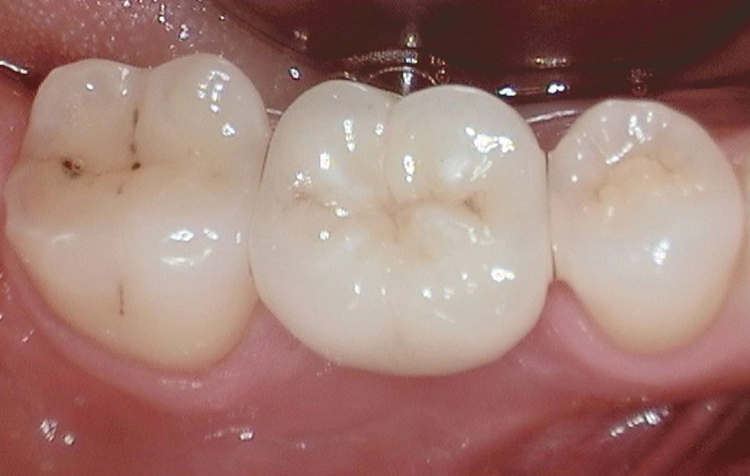

Möchte man im D1-/D2-Knochen „Bone-Level“ Kavitäten aufbereiten, so empfehle ich eine „krestale Entlastung“ im kortikal-krestalen (!) Bereich: Für ein ø 3,5 mm Implantat erfolgt dies mit einem ø 4,0 mm Bohrer, bei einem ø 4,0 mm Implantat (für einen Einzel-Molaren) dann auch final mit einem ø 4,5 mm Bohrer. Wir simulieren so eine Sofortimplantation, bei dem die röntgenologischen Ergebnisse auf Jahrzehnte gesehen ebenso wie das „subkrestale Implantieren“ als sehr gut zu bezeichnen sind.